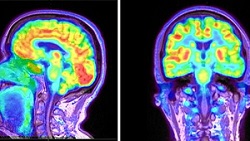

Our mission is to WIDEN ACCESS TO PET IMAGING, reducing gaps and improving biomedical research and diagnostics worldwide, particularly of cancer and neurodegenerative diseases.

EasyPET technology is a new concept for high-resolution PET imaging. Its simplicity allows overcoming the main barriers to the adoption and use of PET: high complexity and cost.

Upgraded systems specially designed and engineered for advanced preclinical imaging research (iPET) and organ-dedicated PET.